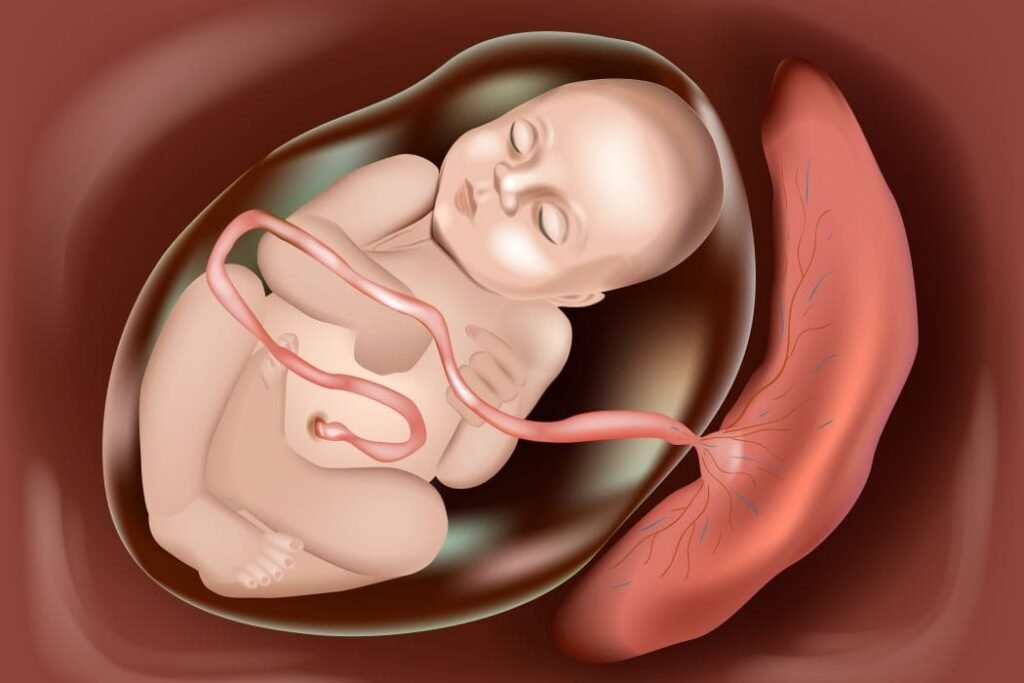

المشيمة هي عضو مؤقت يتكون أثناء الحمل، من وظائفه: نقل الأوكسجين والغذاء من الأم إلى الجنين، وإزالة الفضلات من دم الجنين، وإنتاج هرمونات الحمل والمساهمة في المناعة بين الأم والجنين. ويجب الإشارة إلى أن الدم الذي بداخل المشيمة ليس كله دم الجنين فقط؛ فهناك شبكتان دمويتان منفصلتان تقريبا لدم الأم ودم الجنين.

وتحتوي المشيمة على خلايا جنينية بشكل أساسي، فهي عضو يتطور من البويضة المخصبة (الجنين) ويكون تركيبه الوراثي مطابقاً للجنين وليس الأم. وهي أيضا عضو غني بالخلايا الجذعية الجنينية، ودم الحبل السري، وخلايا الأرومة الغاذية التي تساعد في التغذية والتبادل بين الجنين والأم.

وللذي يتساءل، الخلايا الجنينية من أهم أنواع الخلايا. تتصف أنها متعددة القدرات بمعنى أنها يمكنها التحول إلى أي نوع آخر من خلايا الجسم إلا المشيمة نفسها، مثير للاهتمام، أليس كذلك؟ وتتميز بقدرتها العالية على الانقسام الذاتي والتمايز إلى أي نوع من خلايا الجسم البشري، مما يجعلها أداة واعدة في الطب التجديدي، وعلاج الأمراض المستعصية وفحص الأدوية.

ويوصي الأطباء بعدم قطع الحبل السري بسرعة إلا بعد مرور دقيقة إن لم يعرض الأمر الجنين للخطر. لكي تنتقل كمية إضافية من الدم للطفل وتقليل خطر فقر الدم لدى الرضع.